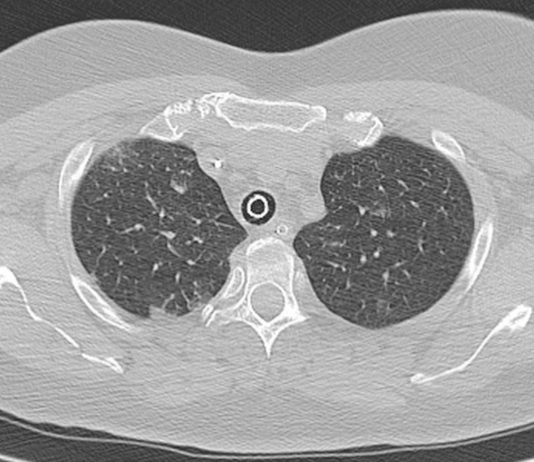

55-year-old

female patient affected by obesity and systemic lupus erythematosus in

treatment with steroids. Asymptomatic, exposure to Covid-19 patient (husband).

Swab negative.